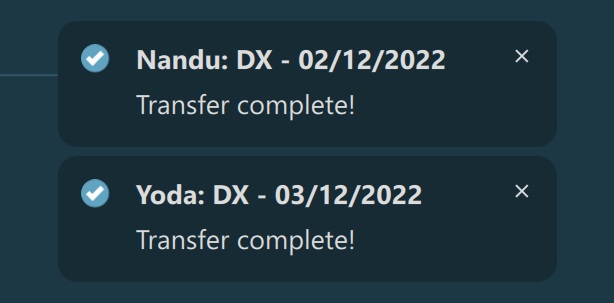

Completed transfers of images are indicated in two different ways in VisioVIEW. The Transfers button has a blue dot in the top right corner to indicate unopened completed transfers, which is automatically removed as soon as the user opens the

popup. In addition, as soon as a transfer of a study is completed, a notification of the completed transfer pops up in the bottom right corner of the Preview Pane, with the latest notification stacking up above the older ones. The notifications

are visible for about three seconds before automatically disappearing.

Transfer of images has been completed: